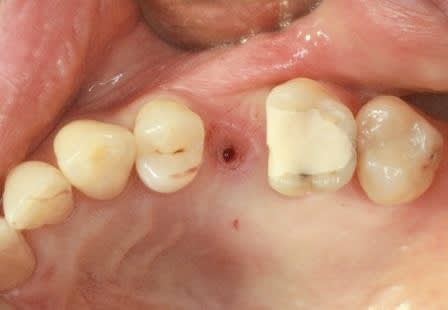

je voulais parler de ce fact pour les implants courts:minimum 4mm os vertical peut suffire (pour eviter un sinus lift externe de tatum) . dans ma pratique depuis quelques années je vois que ca marche , quelques cas cliniques des années passées.

j´ai oublié : 4mm plus 2mm( gagnés par un sinus lift interne)

oui effectivement c est preferable des implants pas agressifs, sur la photo 7 on se rends plus compte que la pointe est plate...